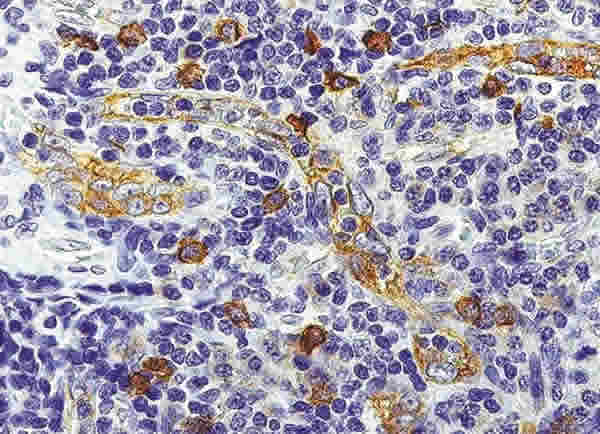

Fig. .8: Células dentríticas plasmocitoides (CDPs). Mayor detalle de la zona parafolicular de un ganglio linfático normal. Se observan varias CDPs alrededor y en la pared de varias VEA. Las CDPs expresan antígenos de superficie que les permiten migrar a través de las VEA para alcanzar la zona T de los tejidos linfáticos y llevar a cabo su función inmunoestimuladora y de CPA (ver texto). Inmunohistoquímica para CD123.